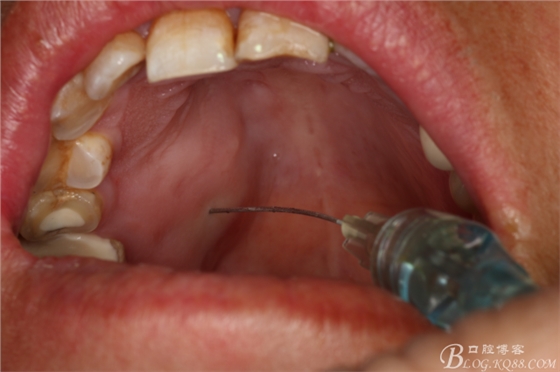

圖5.唇側(cè)局部浸潤(rùn)麻醉

圖6.腭側(cè)局部浸潤(rùn)麻醉